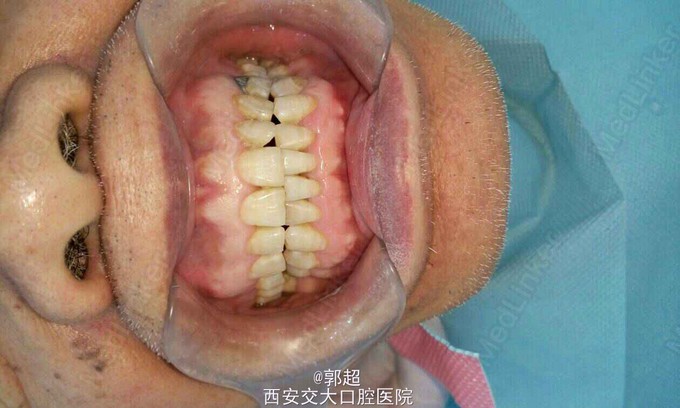

46缺失,牙槽脊轻度吸收,咬合间隙可。咬合异常,一侧后牙咬紧,对侧开牙合,下颌正中咬合时,两侧牙列颊尖均有1mm间隙,反复检查纠正还是如此。